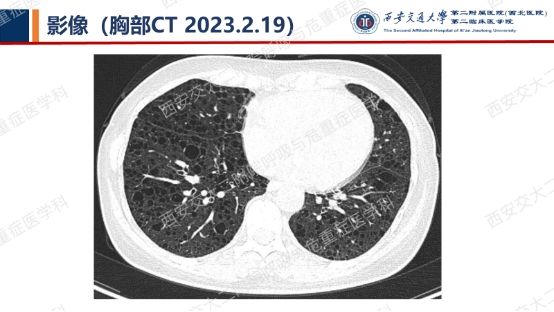

阅影探案,析病寻踪 // 第一期(上)

影像方寸藏玄机,同影异病辨真章。让我们一起抽丝剥茧,揭秘医学真相,解锁临床那些有意思的病例谜题吧!

结合以上患者病史及胸部CT,第一诊断分别考虑???欲知答案,且看后期!!!